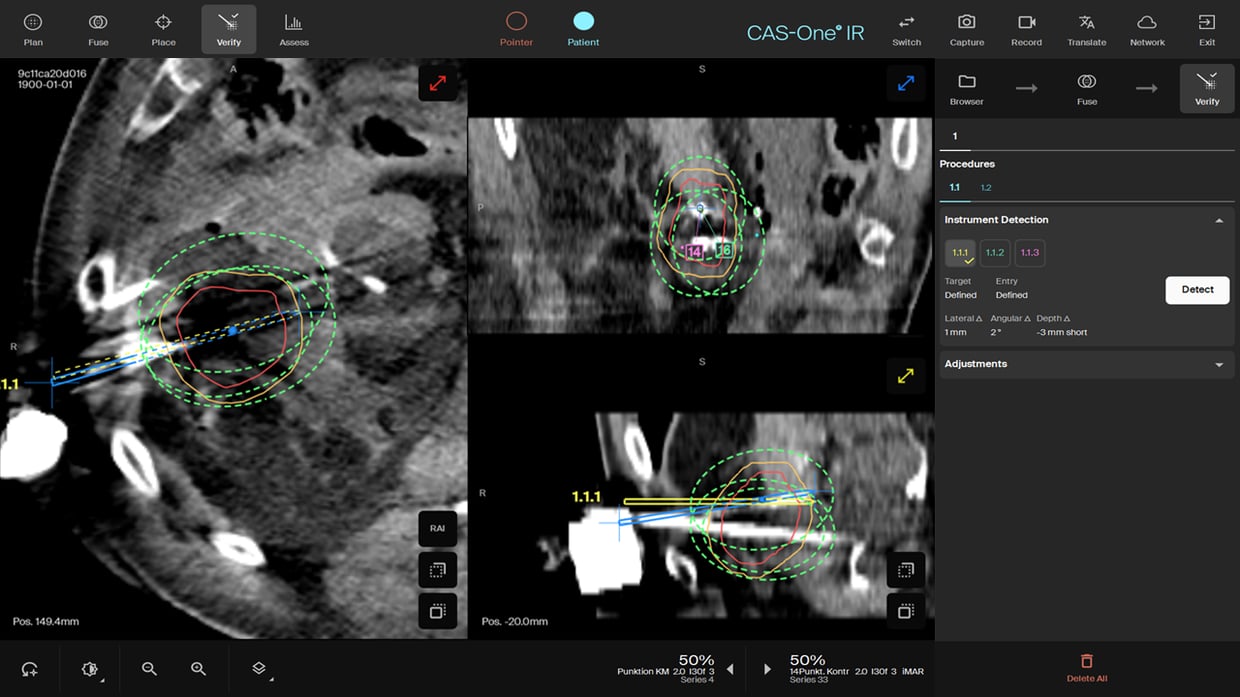

Verify scan showing the position of the three IceForce with 1.5cm separation and full coverage of the tumor. The colon has been pushed away by the hydrodissection.

- Needles were all placed in one insertion push with less than 1mm lateral deviation